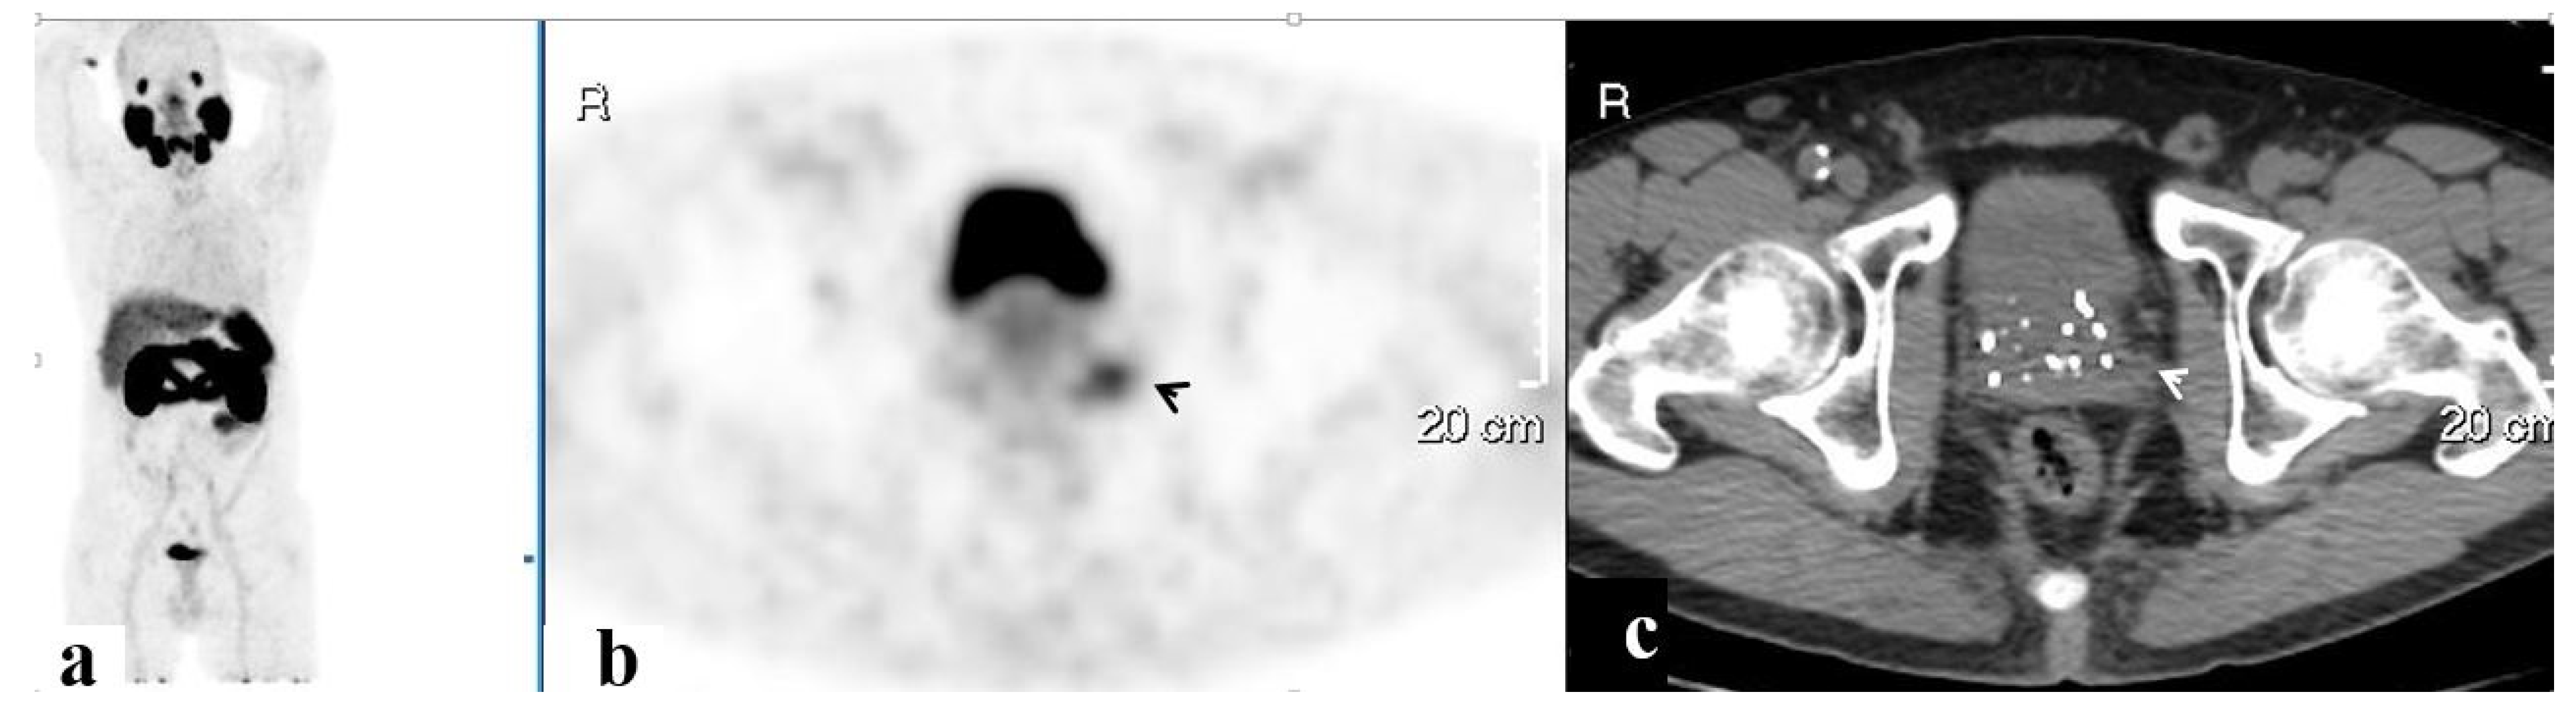

3.4. Salvage Radiation Therapy

3.4.2. The Site of Salvage Radiotherapy

| Prostate | 37 | 10.0 ± 6.4 | 2.1 ± 1.1 | 11 |

| SV | 23 | 8.6 ± 5.9 | 0.5 ± 0.5 | 7 |